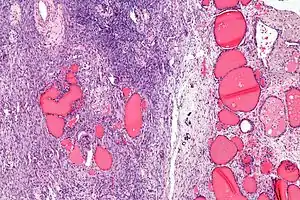

| Micrograph of a struma ovarii. Characteristic thyroid follicles are seen on the right, and ovarian stroma on the left. H&E stain. | |

a-c)Immunohistochemical (CK19, galetin-3, HBME-1) staining of malignant struma ovarii tissues

Low magnification Struma ovarii